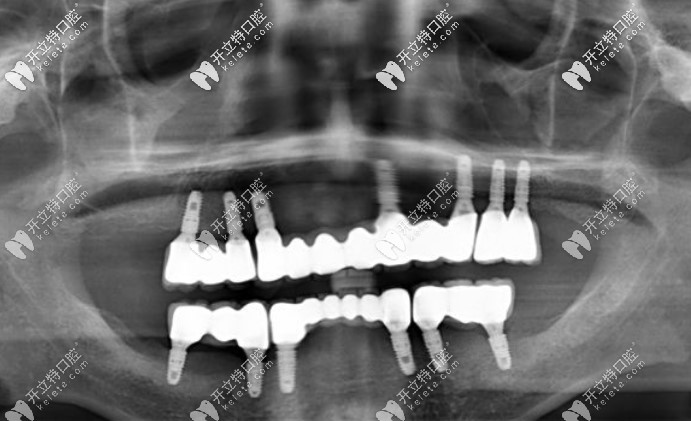

全口種植后拍的片子▼